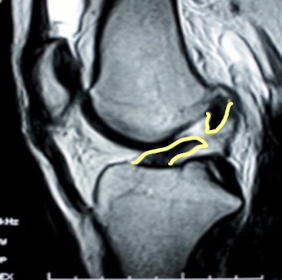

Q

Which ligament is torn?

A. patellar

B. MCL

C. LCL

D. ACL

E. PCL

A